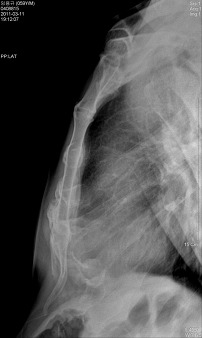

*흉부 측방향 촬영법(Chest lateral )

검사목적

Left Lateral에서는 좌측 심장과 폐의 병소를, Rignt Lateral에서는 우측 심장과 폐의 병소를 진단하기 위해 사용

Central Ray

T-6 높이의 정중면에 수직으로 입사

Check Point

척주뒤의 Rib이 겹쳐서 보여야 한다

흉골이 회전되지 않아야 한다

Apex, CP angle은 포함되어야 한다

심장과 diaphragm의 윤곽은 선명하게 나타나야 한다

Hilum이 영상의 중앙에 나타나야 한다